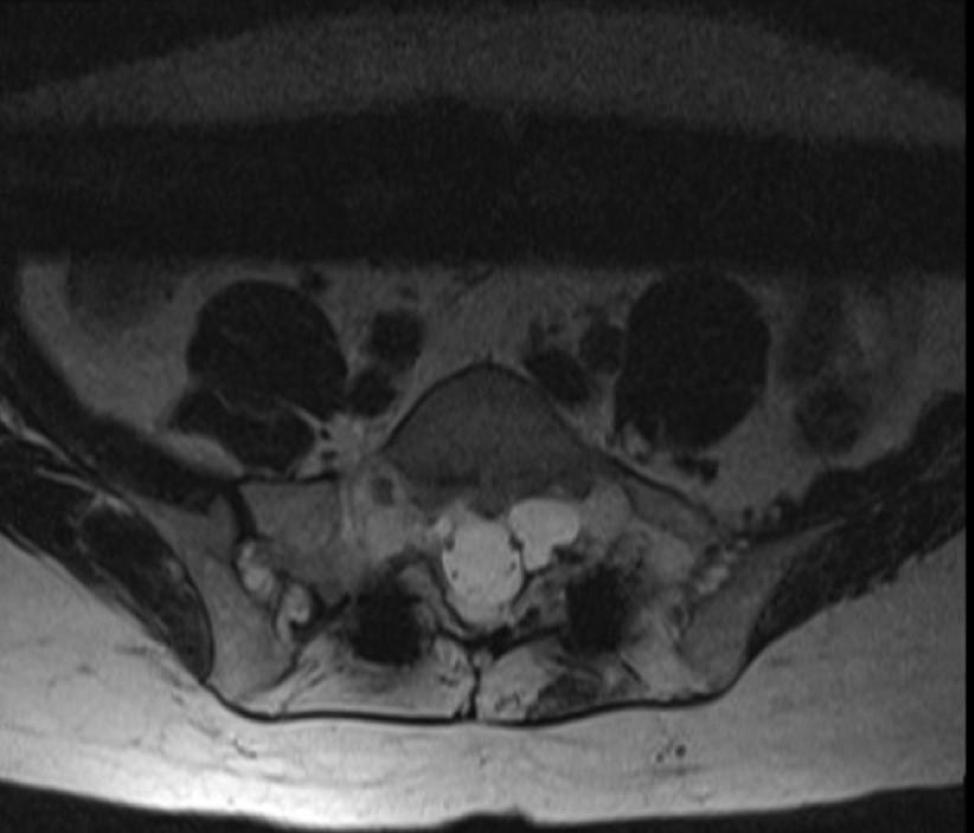

Tarlov cysts were first described by Isadore Max Tarlov in 1938. Tarlov was a neurosurgeon who worked at McGill University and discovered these perineural cysts while dissecting cadavers. He initially described these lesions as anatomic variants with unclear clinical significance. These cysts are filled with cerebrospinal fluid (CSF) and pouch out from the nerve roots. The cysts form in the layers between the perineurium and the endoneurium. They most commonly occur at the sacral level but can also occur in the lumbar and cervical spine (Figure).

Figure. Axial magnetic resonance image of left S1 nerve Tarlov cyst.